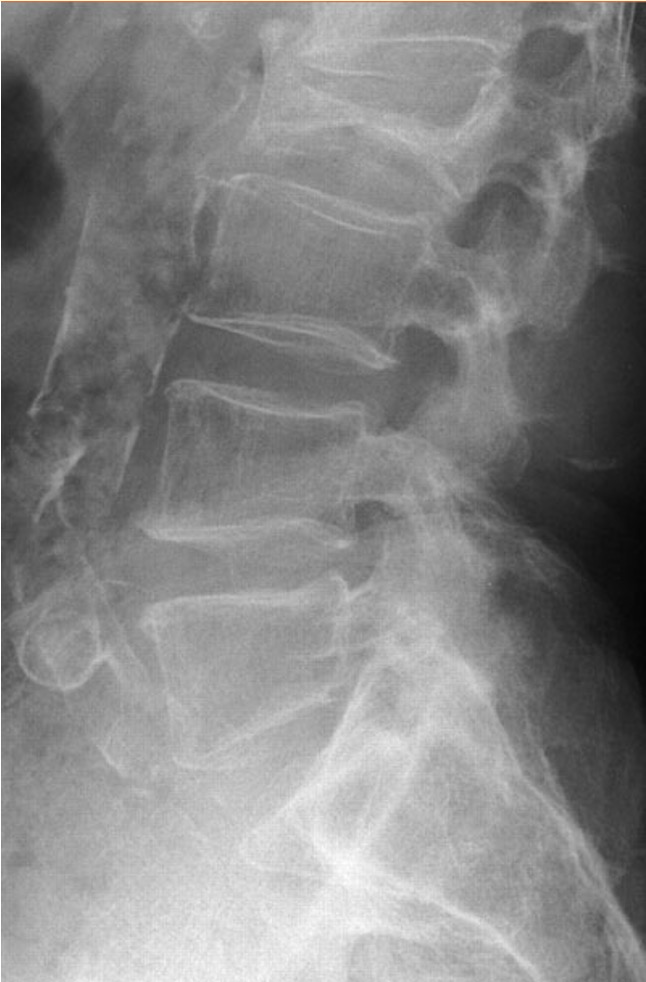

X-ray

75% have abnormality

Winking Owl Sign / Pedicle loss on AP

Lytic / Sclerotic lesion

- need 30% bone loss to see lytic area

Vertebral body collapse

CT Scan

Define

- bony abnormality

- deformity

- potential instability

Lumbar